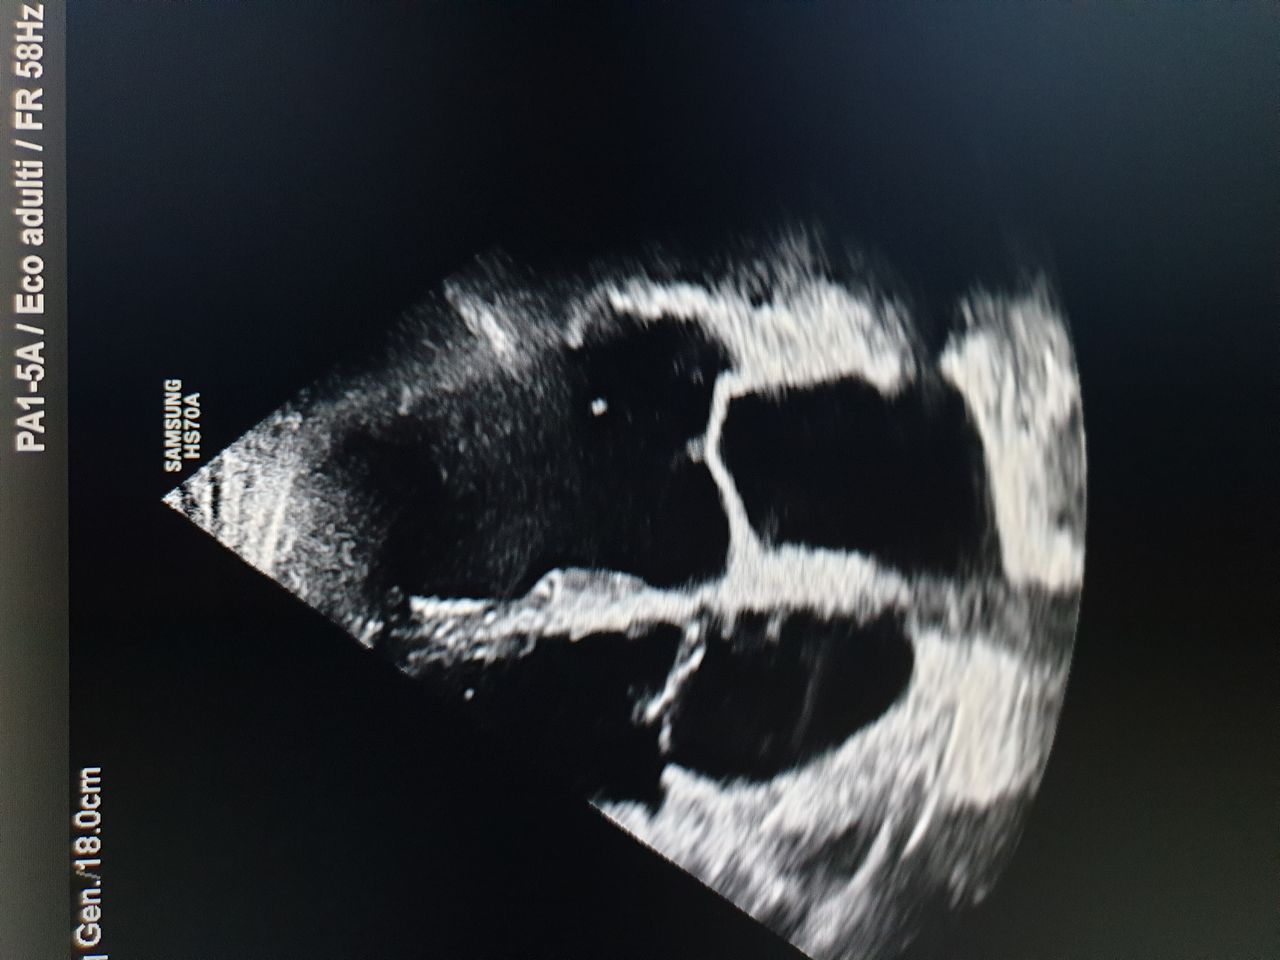

Foto e video